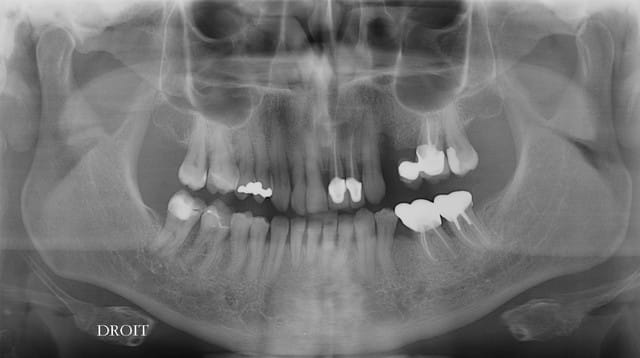

Une petite pano?

Pano, bilan radio.

peux tu nous renseigner sur la mobilité au niveau de la 11 et 12 parceque le reste est gerable.

Mobilité de 11-21-23 ?

échelle de 1 à 4

12 :un bon 3

11 :3

21 :2.5

22 :2.5